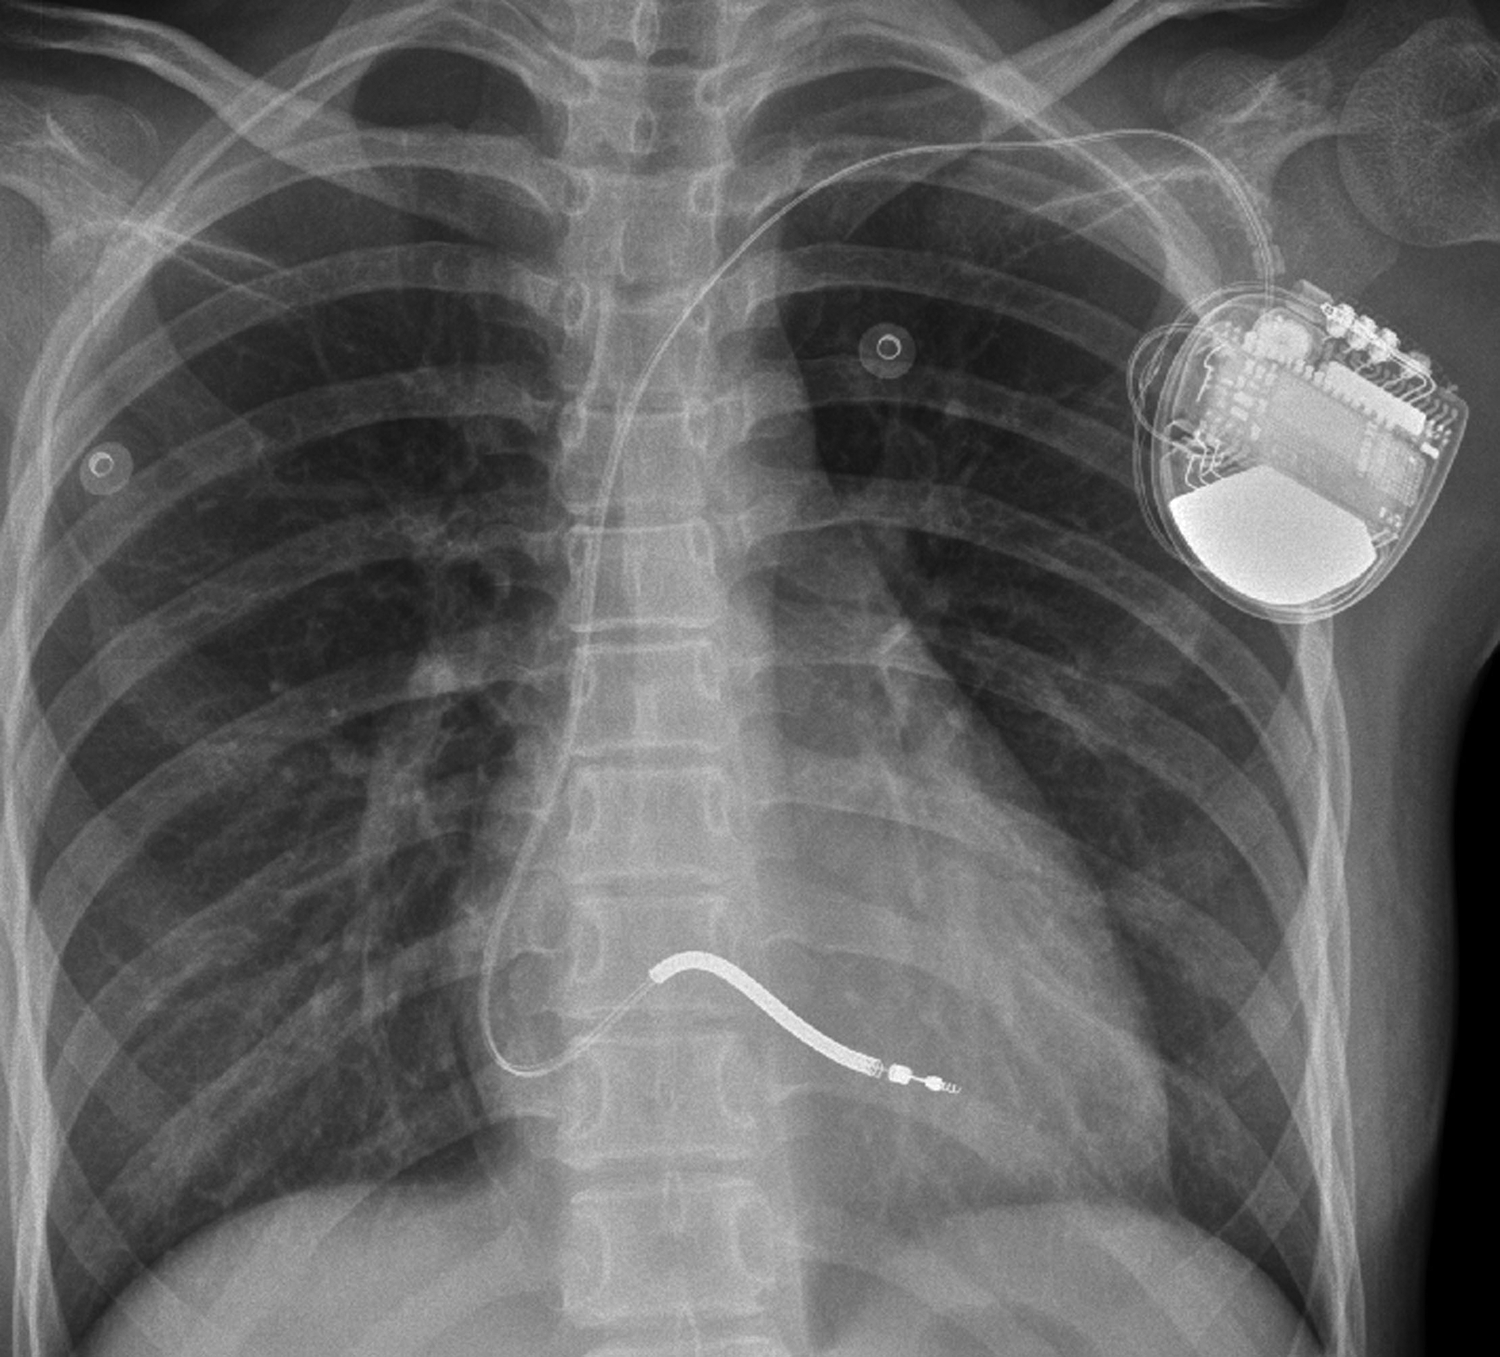

After 9 months, the child suffered from syncope and convulsions again during housework. She was transferred to our hospital after cardiopulmonary resuscitation for 2 h. The ECG showed frequent multisource VT with Tdp (Figure 1C). Temporary subclavian pacing was given to the patient, and vasoactive drugs were used to maintain circulatory stability. Oral propranolol tablets were adjusted to 1 mg/kg every 8 h, and the patient received intravenous potassium and magnesium supplementation. The Holter ECG showed that the incidence of ventricular arrhythmia was 19,924 beats in 24 h with no occurrence of Tdp. Considering that the child had syncope after drug treatment, she was implanted with an implantable cardioverter defibrillator (ICD) under general anesthesia after 7 days of stabilization (Figure 3). Her parents were informed that she needed activity restriction and exercise reduction.

Figure 3

Chest x-ray after the implantation of the implantable cardioverter-defibrillator.